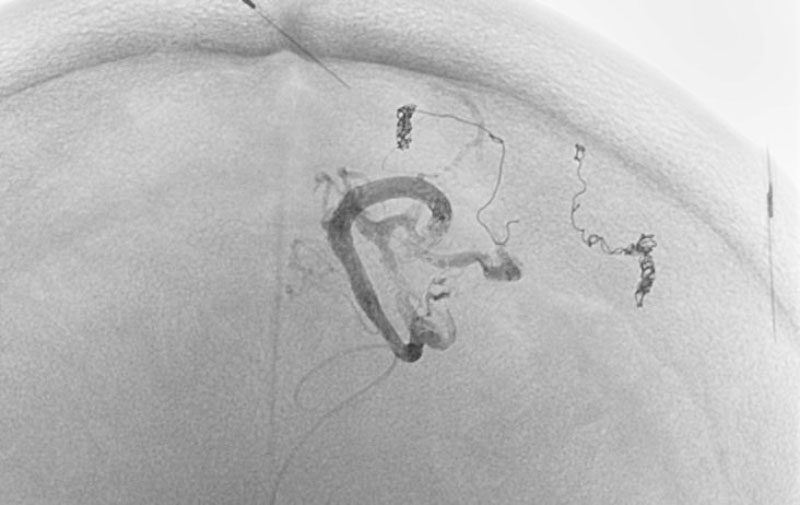

'25年10月

くも膜下出血

前交通動脈瘤破裂

60代

救急外来

No.1588 手術前

No.1588 手術中

No.1588 手術後